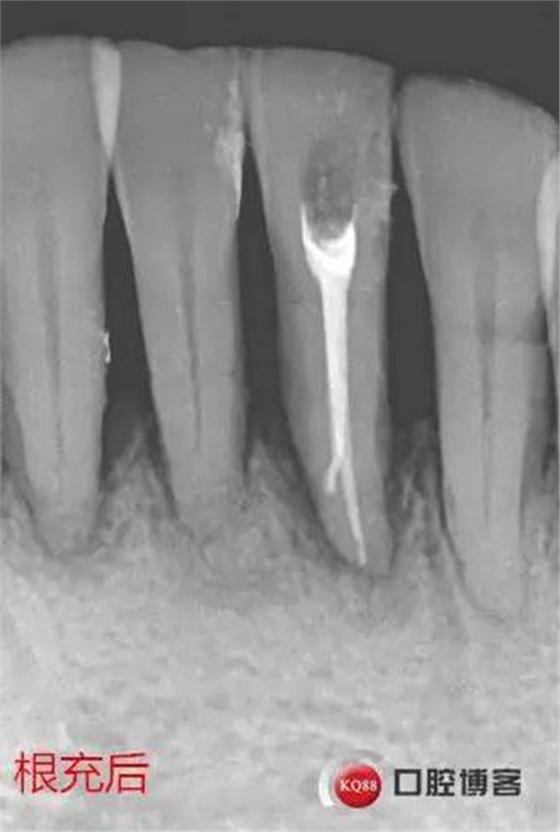

处理:上橡皮障,31开髓,测工作长度17mm,含氯冲洗液冲洗,机扩至04锥度30#,超声荡洗,一次性根充。33-43牙齿邻接处super bond粘结固位,行松牙固定。调合。拍根充术后片,未达根尖,怀疑遗漏根管,去除根充物后,继续探查根管,找到舌侧根管,测长度20mm,时间原因,未行扩根,氢氧化钙暂封。

事后再次查看术前片,可以看到两个根管影像,忽略了。

处理:31去暂封,疏通根管,冲洗,试尖,拍片,根充,拍片,恰填,根尖孔外无多余药物渗出。树脂充填开髓孔。33-43树脂纤维带固定,调合抛光。